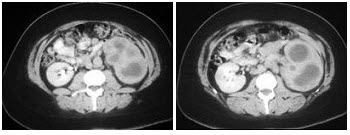

C.影响生精功能导致不育

D.输精管闭塞导致不育

E.以上都不是

23、单项选择题 新月样空气征见于()

A.肺曲霉菌病

B.肺脓肿

C.农民肺

D.肺泡蛋白沉积症

E.肺类风湿性病

24、单项选择题 CT显示颈前三角区囊性占位,可见钙化,囊壁有轻度增强,颈动脉受压与颈内静脉分离,最可能的诊断为()

A.动脉体瘤

B.鳃裂囊肿

C.神经鞘瘤